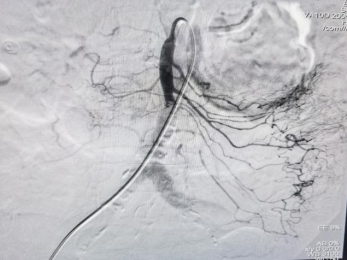

有了成功的经验,次日,在面对同样83岁高龄的另一位女性肺动脉栓塞患者,王启伦主任在得到患者及家属同意后,与聊城市医院张峰主任为患者实施双肺动脉造影+左肺动脉抽吸取栓、下腔静脉滤器植入术,手术顺利完成。

患者手术前后造影对比图: